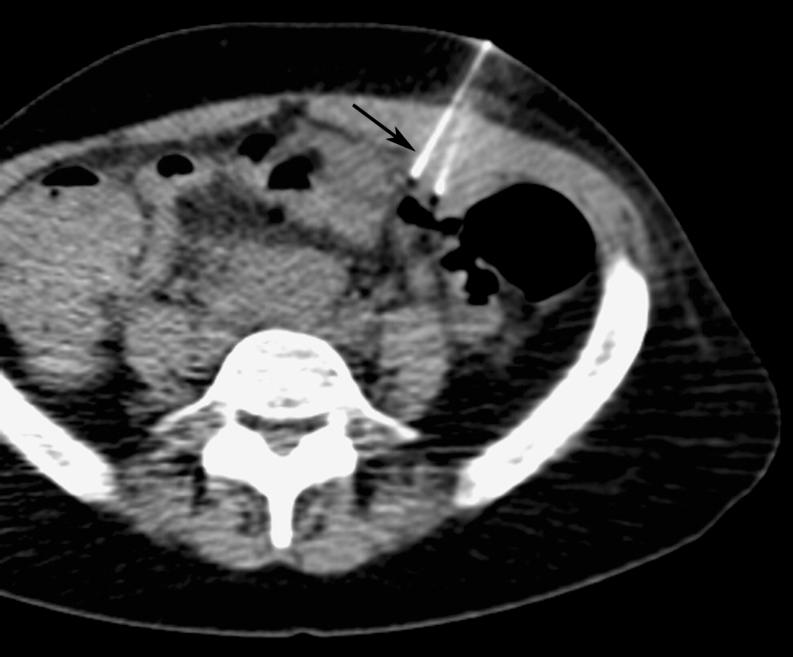

Omental cakes typically are associated with ovarian carcinoma, as this is the most common malignant aetiology. Nonetheless, numerous other neoplasms, as well as infectious and benign processes, can produce omental cakes. METHODS: A broader knowledge of the various causes of omental cakes is valuable diagnostically and to direct appropriate clinical management. RESULTS: We present a spectrum of both common and unusual aetiologies that demonstrate the variable computed tomographic appearances of omental cakes. CONCLUSION: The anatomy and embryology are discussed, as well as the importance of biopsy when the aetiology of omental cakes is uncertain.